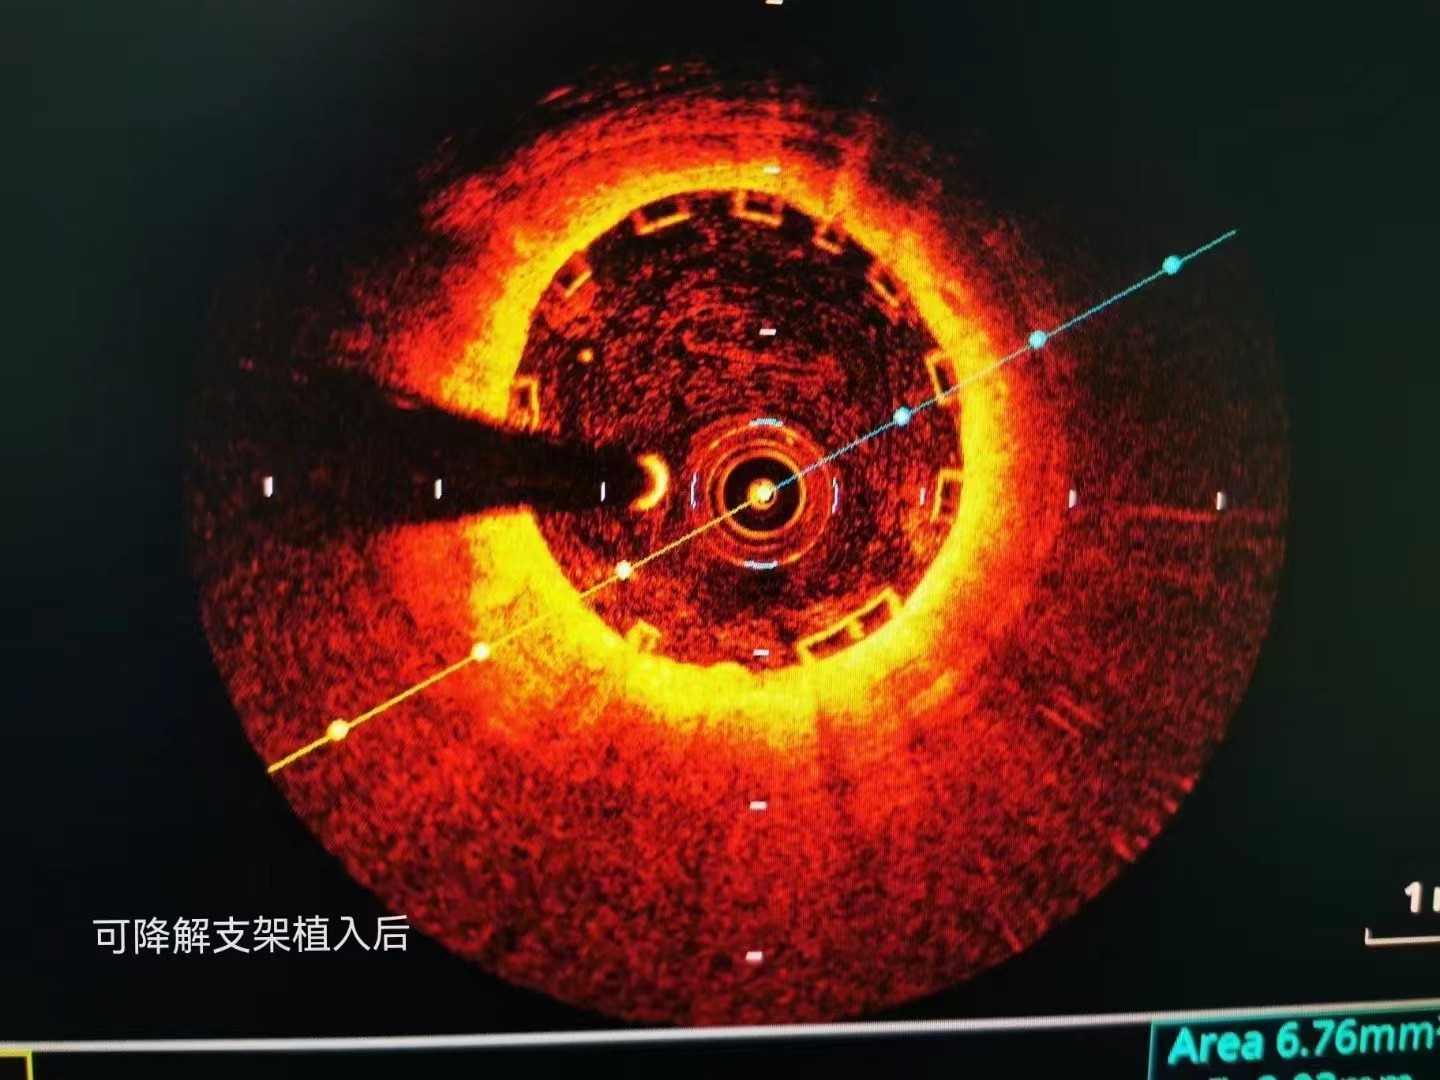

祝賀大連醫(yī)科大學(xué)附屬第二醫(yī)院醫(yī)院趙昕專家團(tuán)隊(duì)成功為患者植入Xinsorb生物可吸收支架! 精準(zhǔn)操作,完美貼壁

祝賀大連醫(yī)科大學(xué)附屬第二醫(yī)院醫(yī)院趙昕專家團(tuán)隊(duì)成功為患者植入Xinsorb生物可吸收支架!

精準(zhǔn)操作,完美貼壁

祝賀大連醫(yī)科大學(xué)附屬第二醫(yī)院醫(yī)院趙昕專家團(tuán)隊(duì)成功為患者植入Xinsorb生物可吸收支架!

精準(zhǔn)操作,完美貼壁